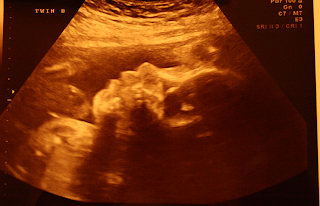

I was scheduled for an appointment tomorrow morning but this morning my doctors office called and asked me to come in today to get my ultrasound done to check on the babies lungs. I was actually really glad because its been a long and rough week waiting for this. I'm happy to say that as of right now everything is ok. The fluid in her lungs has actually decreased a little. That just means more time for these sweet girls to spend kicking around in my belly! They sure do kick and move all over because they actually changed sides. Baby A (who we decided is Ava) is normally on my right side but she is now on my left and Baby B (Teagan) is now on my right. My dr was shocked! She didn't think they would be able to move like that. Well they sure did! It was good because she was able to get views of their heart that she couldn't get before. So for now things are going ok. I'm going to be going to the doctor once a week now though for an ultrasound to check on them and watch that fluid. I will take the good news for this week though. Here are a few pictures of Ava. The picture says Baby B because the girl doing my ultrasound didn't know that they had flipped like they did so she was going off how they are normally positioned.